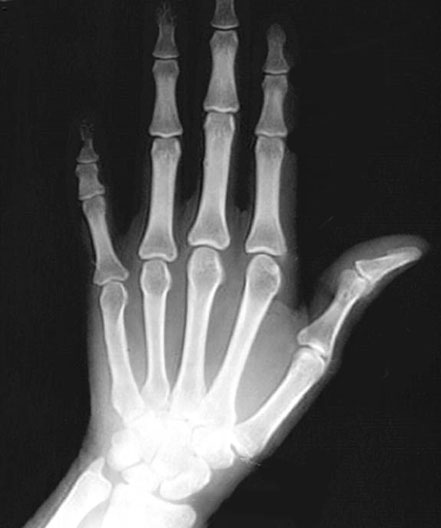

Hand X-Ray

Roll mouse over image to display labels.

1. Styloid Process of Ulna

2. Pisiform bone

3. Hamate bone

4. Lunate bone

5. Scaphoid bone

6. Trapezium bone

7. Capitate bone

8. 5th metacarpal bone

9. 5th Proximal phalanx

10. 5th Middle phalanx

11. 5th Distal phalanx

12. 1st Proximal phalanx

13. 1st Distal phalanx